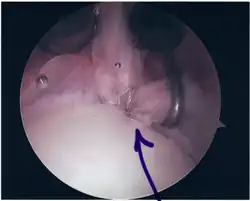

Surgical treatment of SLAP tears has become more common in recent years. The success rate for repairing isolated SLAP tears is reported between 74-94%.[10] While surgery can be performed as a traditional open procedure, an arthroscopic technique[11] is currently favored being less intrusive with low chance of iatrogenic infection.[12]

Procedure

Following inspection and determination of the extent of injury, the basic labrum repair is as follows.

- The glenoid and labrum are roughened to increase contact surface area and promote re-growth.

- Locations for the bone anchors are selected based on number and severity of tear. A severe tear involving both SLAP and Bankart lesions may require seven anchors. Simple tears may only require one.

- The glenoid is drilled for the anchor implantation.

- Anchors are inserted in the glenoid.

- The suture component of the implant is tied through the labrum and knotted such that the labrum is in tight contact with the glenoid surface.